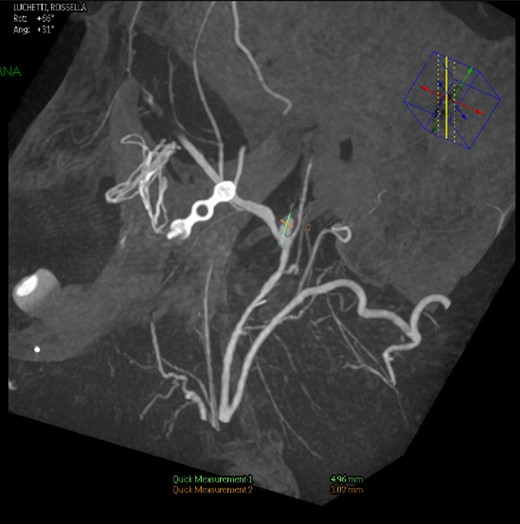

Intraoperative angiography was performed and revealed a PA in relation to the internal maxillary artery, ~1 cm posterior to the left subcondylar region (Fig. 2).

Left common carotid artery angiography in lateral views shows the PA (4.9 × 3 mm).